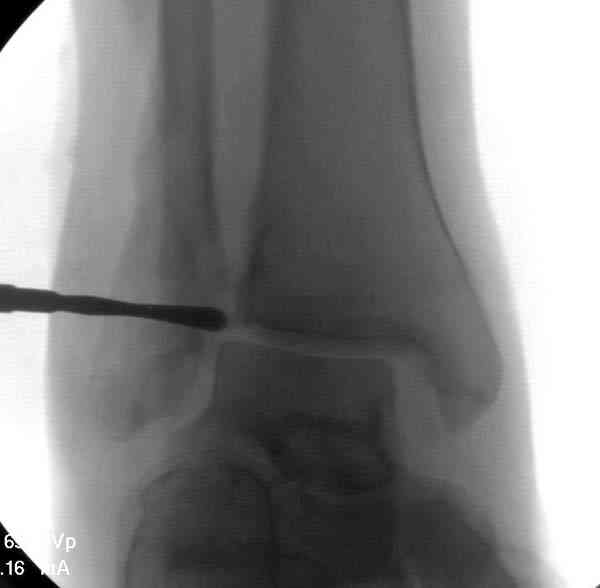

Здесь представлено решение похожей проблемы. Больной в течение года

лечился консервативными мерами, и боли в голеностопе были основным

показанием к операции.

Проведена обычная стандартная процедура по исправлению

неудовлетворительного состояния голеностопного сустава, где кроме

удлинения малоберцовой с применением compression tension device за

проксимальный конец пластины, проведено замещение трикортикальным

графтом из крыла, освобождение синдесмоза и медиальной щели от

фибротических масс с фиксацией.